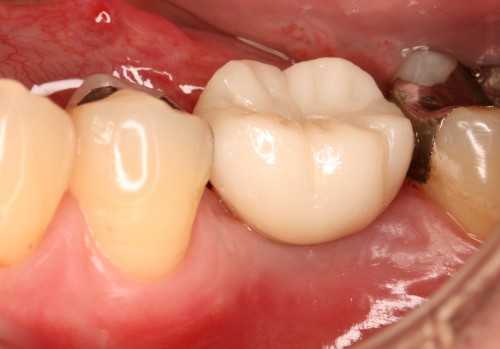

下両奥歯 被せ物装着後